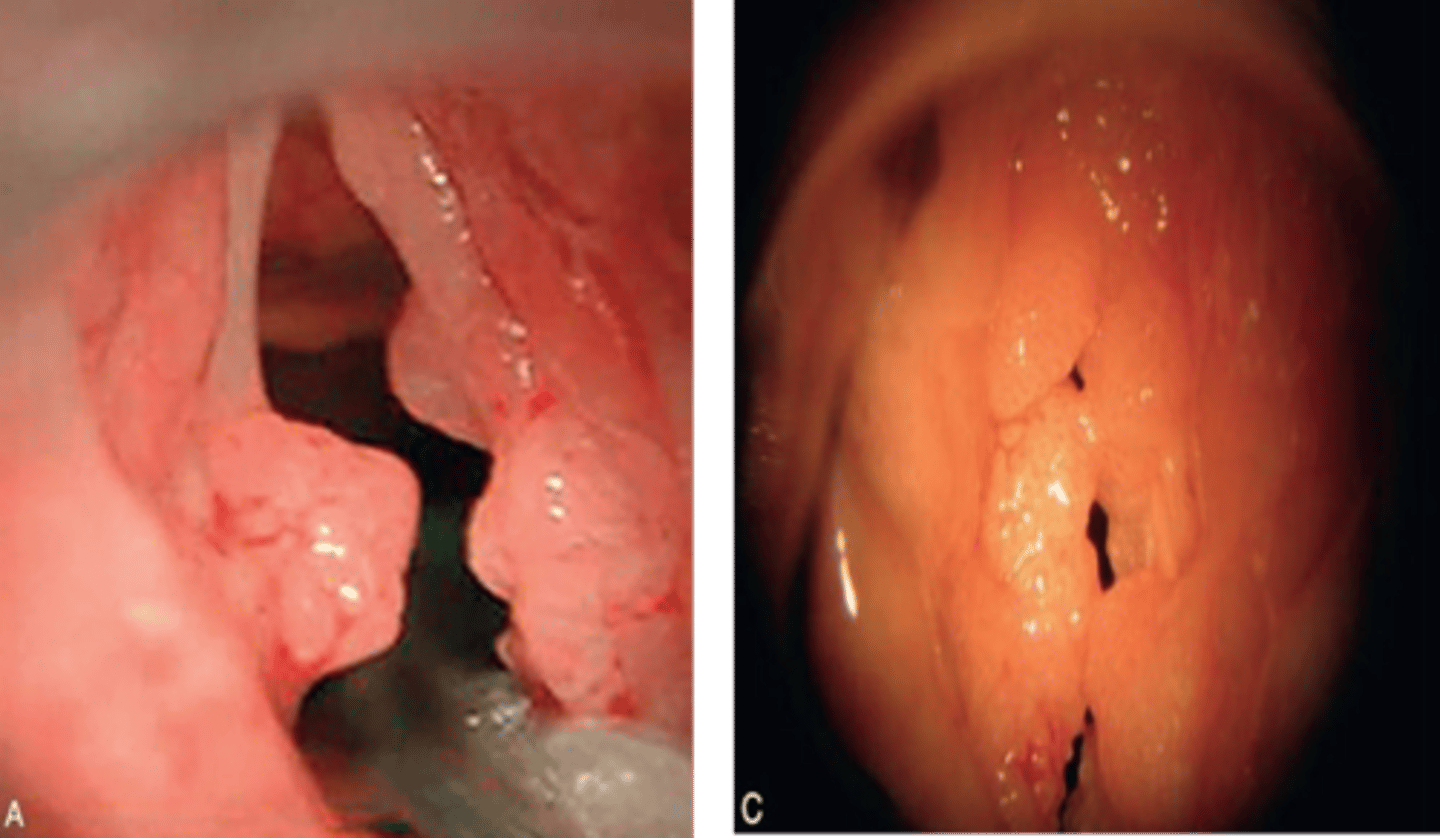

What HPV subtypes cause recurrent respiratory papillomatosis (RRP)?

HPV 6 and 11

How do you treat recurrent respiratory papillomatosis (RRP)?

constant surgery removal (benign)

recurrent respiratory papillomatosis (RRP)

papilloma on the vocal cords, larynx, and respiratory tract that are transmitted from mother to child at birth (HPV 6 and 11)